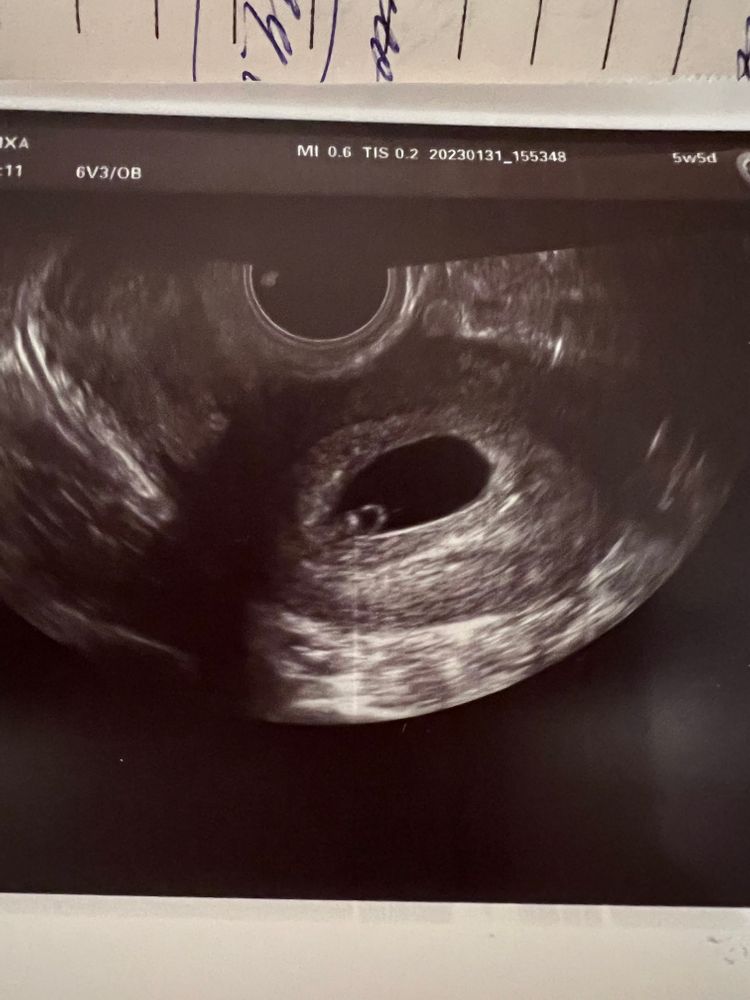

первое узи было 31 января,все нашли и эмбрион с сердцебиением и жм,все хорошо,по месячным срок 5н5д был,а по узи сказали 6н2д,сердцебиение 105 было

первое узи 31.01